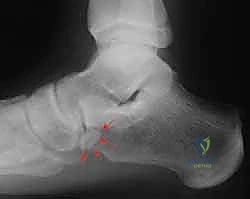

العظم الزورقي الإضافي (Accessory Navicular Ossicle)

في بعض الحالات (حوالي 10-14% من البشر)، يولد الشخص بوجود عظمة صغيرة إضافية ملتصقة بالعظمة الزورقية حيث ينغرس وتر الظنبوب الخلفي. وجود هذا العظم الإضافي يغير من زاوية شد الوتر ويقلل من كفاءته الميكانيكية، مما يؤدي إلى احتكاك مستمر وزيادة الضغط الميكانيكي على الوتر، ويسرع من تدهوره وتمزقه في سن مبكرة مقارنة بالأشخاص الذين لا يمتلكون هذه العظمة.